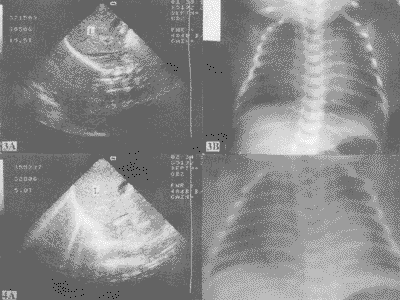

图3A 正常新生儿肝后未见任何回声;3B X线胸片提示心肺正常

图4A 肝脾后见更稀疏的放射状的中高回声;4B 同一患儿的X线显示湿肺

40例正常足月新生儿中, 34例超声检查在肝(脾)后无任何回声, 同一天的X线胸片也提示心肺无异常(图3)。 6例超声见肝(脾)后稀疏的放射状强回声, X线胸片报告为湿肺(图4)。 40例新生儿均无呼吸系统症状, 在生后3~7天相继出院。

一、 正常肺泡是含气的器官, 超声束如果遇到气体几乎全被反射而很难穿透[3]。 本组正常新生儿中超声检查所见的肝(脾)后的薄层光亮反射就证明这个声学特点在正常含气肺脏中的表现(图3)。